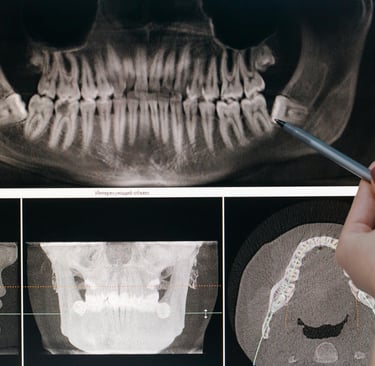

Je réaliserai tous les examens nécessaires (examen clinique, radiographies 2D et 3D, empreinte numérique, photographies…) afin d’établir un diagnostic précis

Je réaliserai tous les examens nécessaires (examen clinique, radiographies 2D et 3D) afin d’établir un diagnostic précis

Reconstructions osseuses : régénération osseuse guidée, greffe osseuse, soulevé de sinus par voie crestale ou latérale

Dans certains cas il est nécessaire de reconstruire l’os et/ou la gencive avant la pose d’implants ou conjointement à celles-ci. Grâce aux nombreuses formations que j’ai effectué dans ce domaine, je suis en mesure de vous proposer des protocoles modernes, minimalement invasifs et reproductibles que je ne manquerai pas de vous expliquer en détail lors de votre consultation si cela s’avère nécessaire.